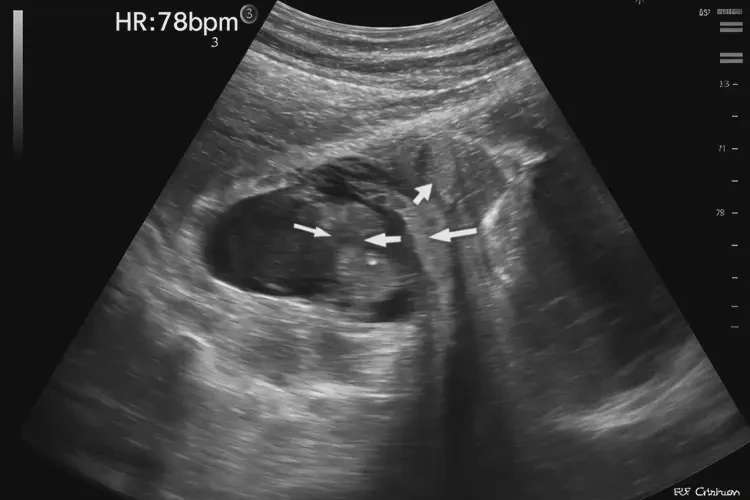

孕18周3天胎心率79怎么回事

胎心率79次/分鐘 在孕18周3天的情況下屬于較低水平。正常胎心率范圍為120-160次/分鐘,低于120次/分鐘可能提示胎心過(guò)緩

胎心率是評(píng)估胎兒健康狀況的重要指標(biāo)之一。在孕18周3天時(shí),胎兒的心臟已經(jīng)發(fā)育成熟,能夠通過(guò)胎心監(jiān)護(hù)儀進(jìn)行監(jiān)測(cè)。正常情況下,胎心率應(yīng)保持在120-160次/分鐘之間,這表明胎兒的心臟功能正常,血液循環(huán)良好。當(dāng)胎心率低于120次/分鐘時(shí),可能存在胎心過(guò)緩的情況,需要引起重視。

孕18周3天胎心率79怎么回事(圖1)